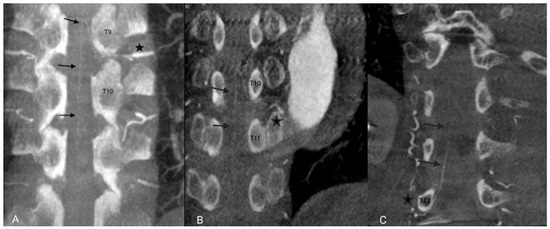

2.2. Diagnostic Angiography Procedure